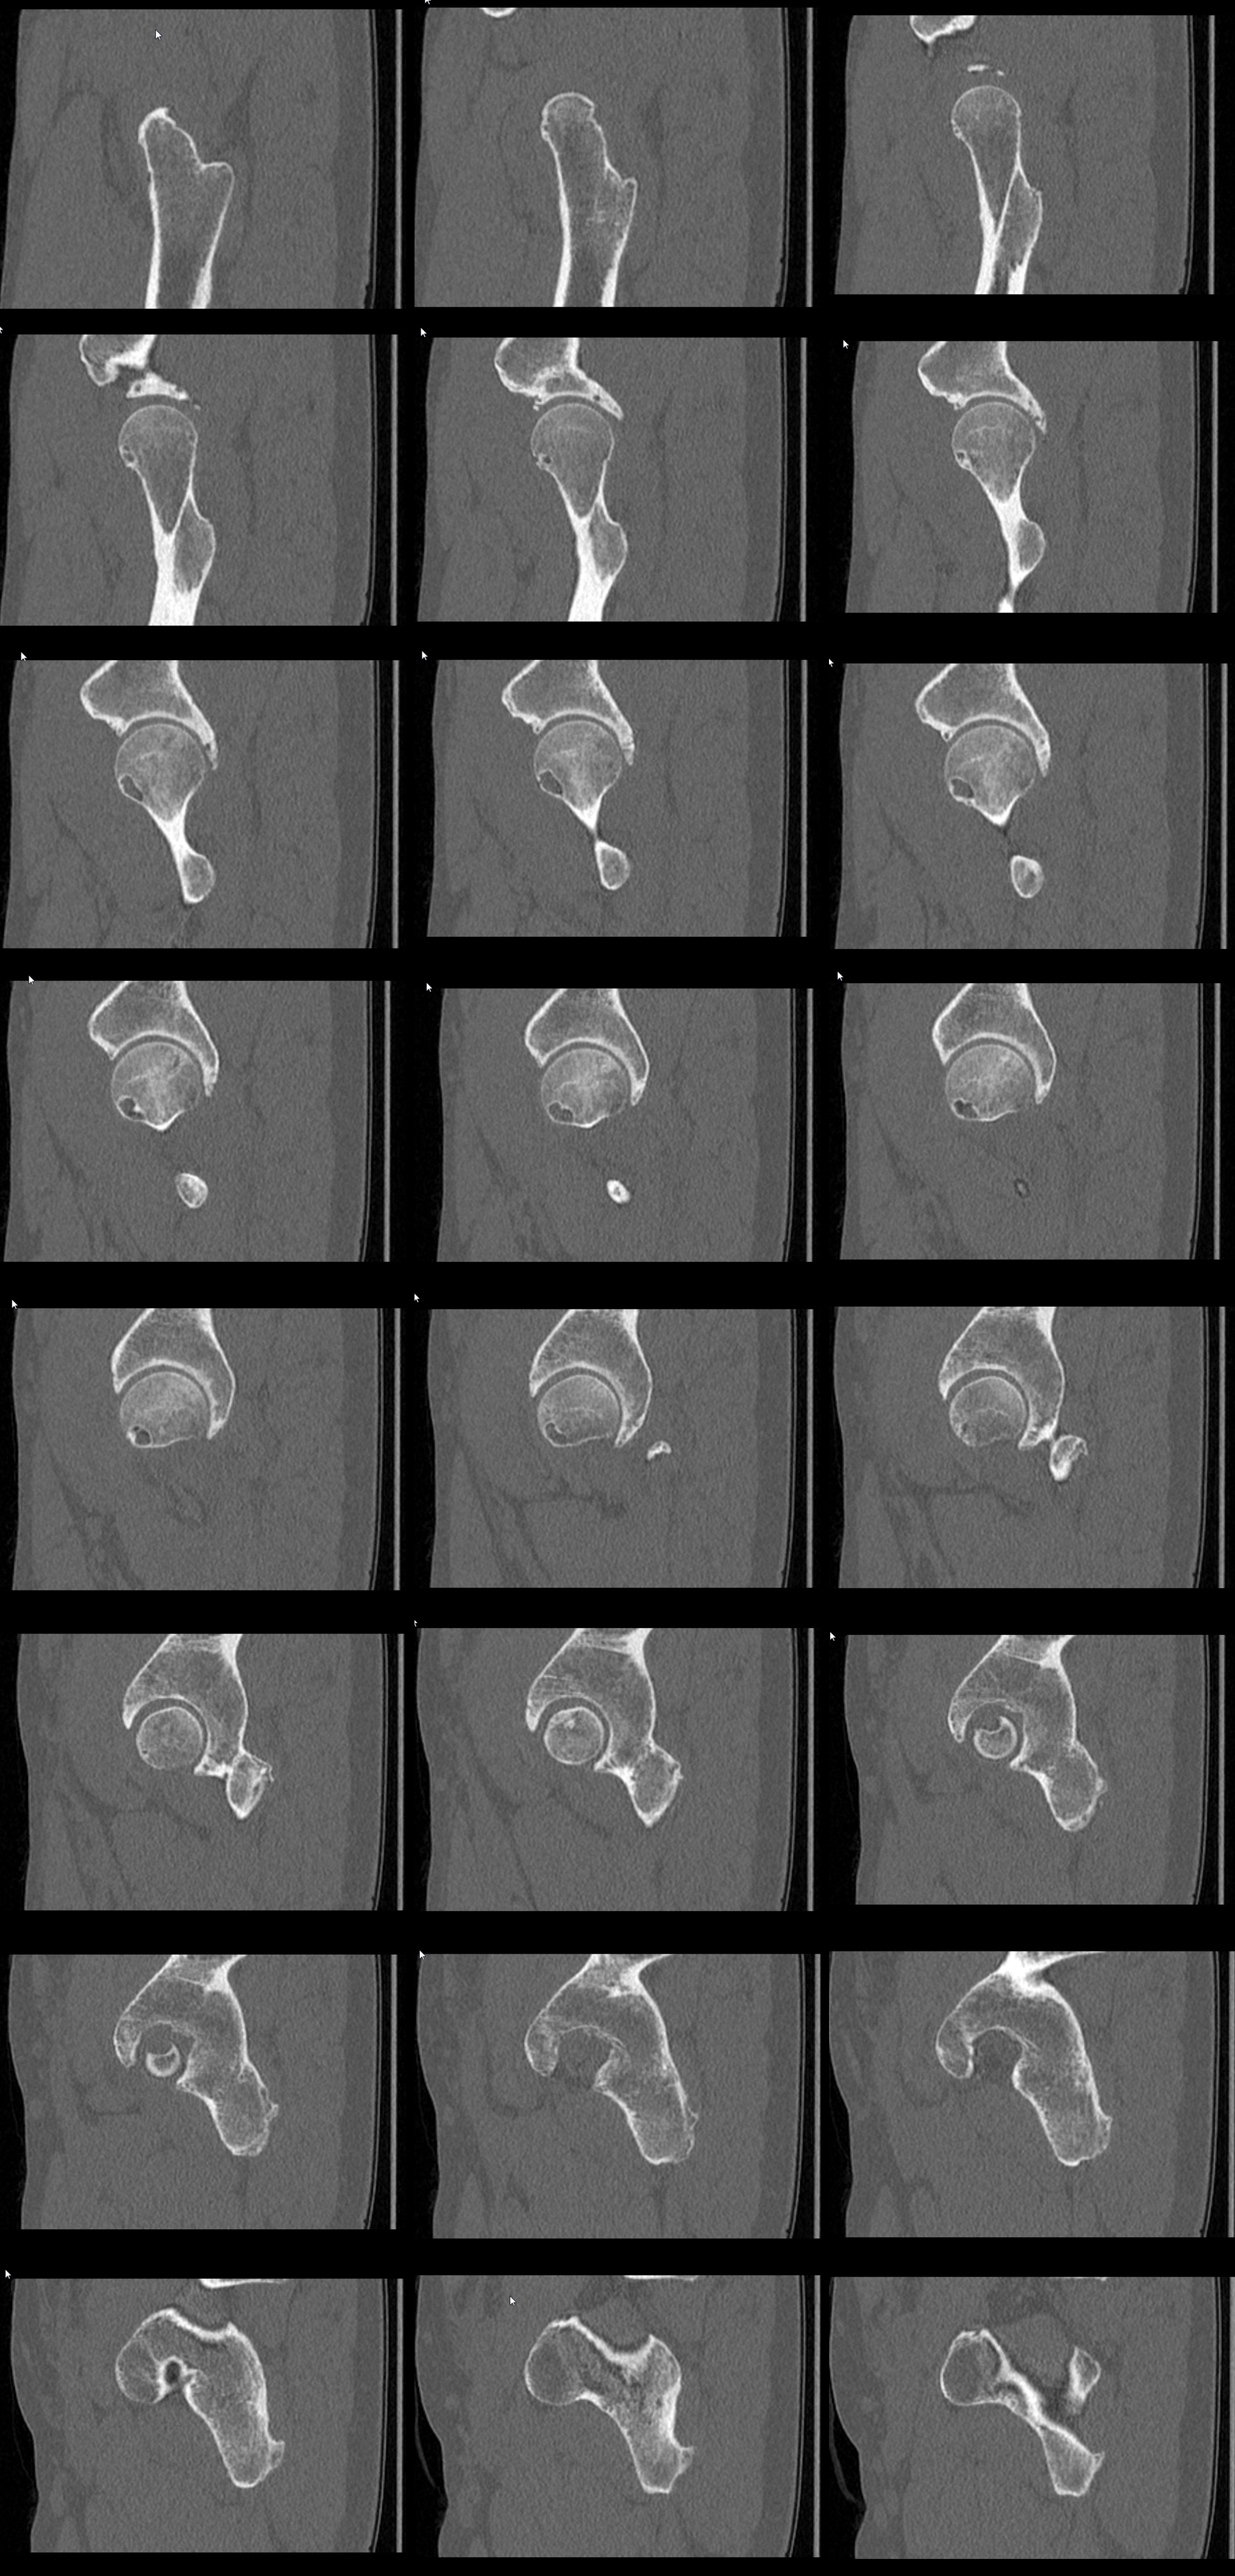

Еще КТ

Выкладываю доп.КТ и сегодня выполним рентгенографию.

Если я правильно понял, по КТ - признаки CAM-импиджмента. Но киста располагается по передне-нижней поверхности шейки и головки бедра. Может ли она являться результатом импиджмента?

И ещё